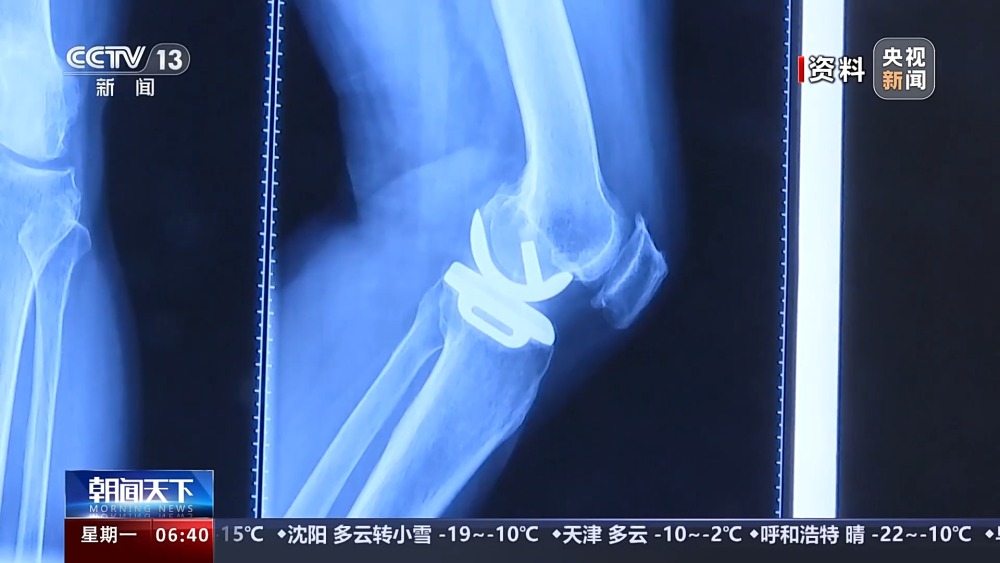

目前,我國有超過1億(yi) 人患有骨關(guan) 節炎,65歲以上人群中,骨關(guan) 節炎發病率接近50%。以前,嚴(yan) 重骨關(guan) 節炎患者主要通過膝關(guan) 節置換手術來維持行走等基本功能。膝關(guan) 節置換手術存在術後關(guan) 節僵硬、長期疼痛等問題。保膝治療包括藥物、理療等保守治療,以及手術治療。

保膝手術主要包括截骨術和單髁置換術,其中截骨術在解決(jue) 患者疼痛症狀的同時,阻止下肢異常應力對膝關(guan) 節的進一步損傷(shang) ,膝關(guan) 節內(nei) 所有軟骨韌帶、半月板都得到了保留。內(nei) 側(ce) 單髁置換術,使膝關(guan) 節外側(ce) 健康的軟骨和半月板得到了保留,膝關(guan) 節內(nei) 外側(ce) 的韌帶維持原有狀態,患者康複後,擁有正常的膝關(guan) 節功能。